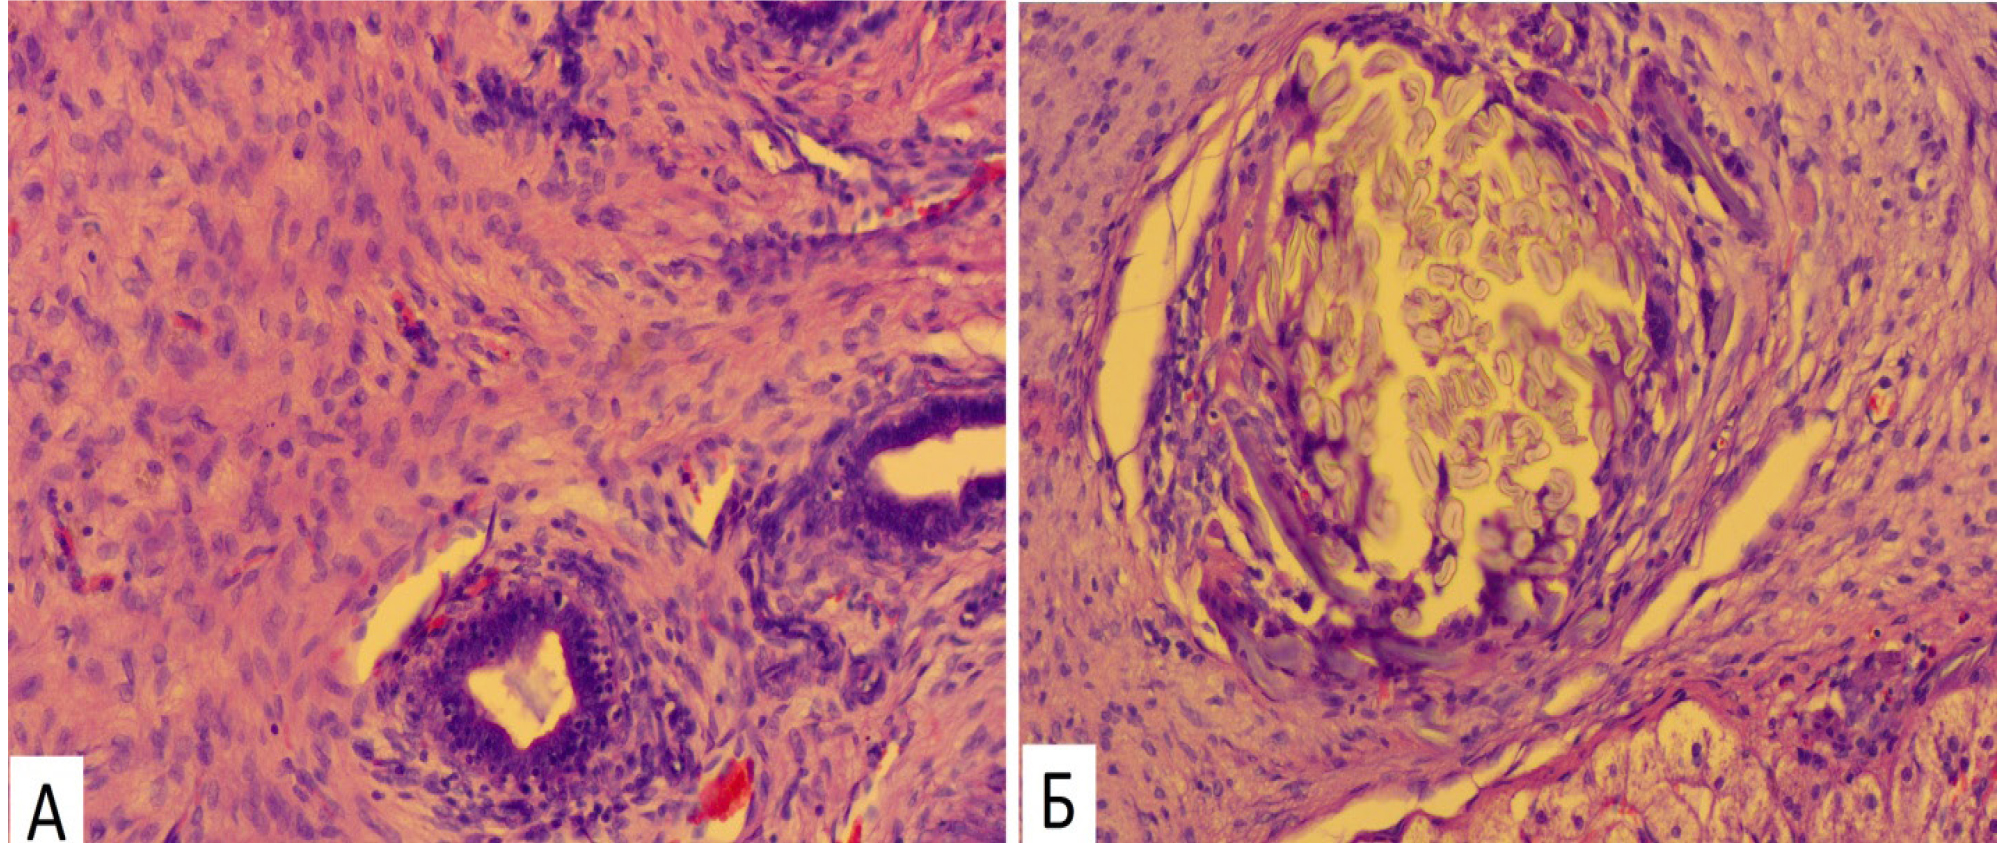

На 14-е сутки эксперимента (ОГ) в формирующейся рубцовой ткани вокруг молселекта G-50 отмечались многочисленные многоядерные гигантские клетки инородных тел (рис. 5А). В это же время в КГ формирующаяся соединительнотканная капсула имела незначительное количество гигантских клеток на рассасывание инородных тел (рис. 5Б).